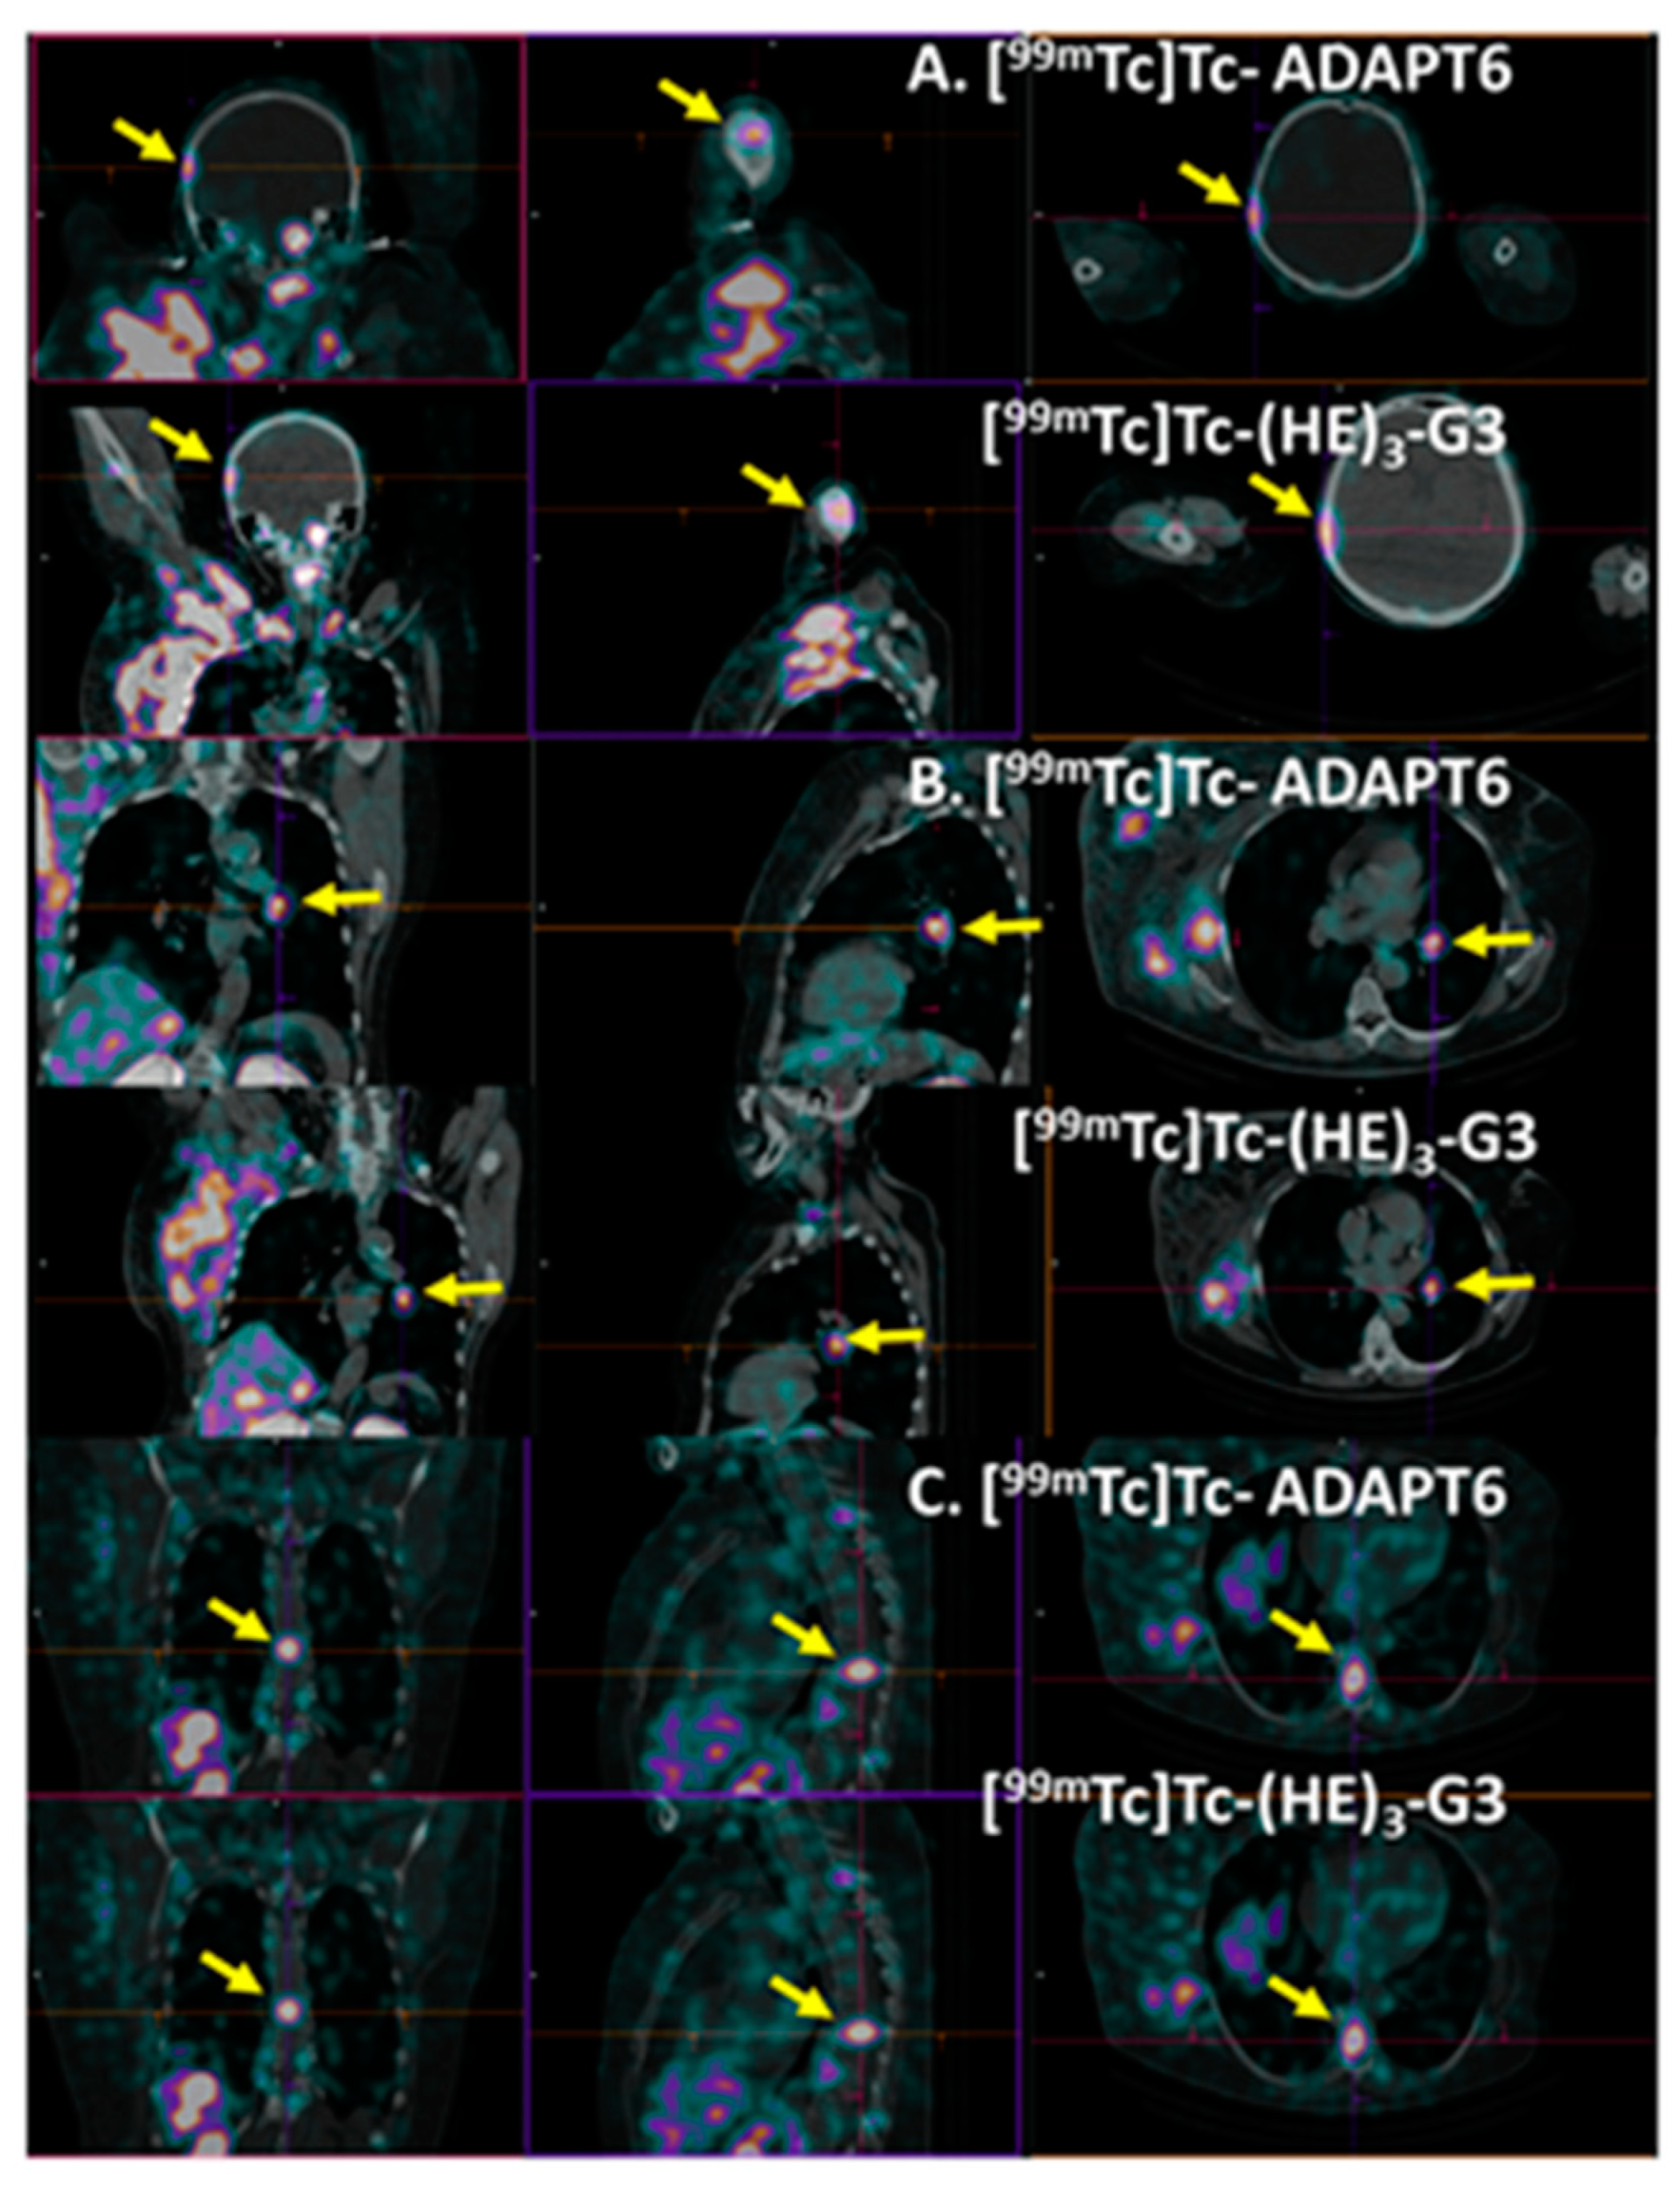

3. Results

4. Discussion